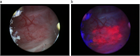

1. PDD(photodynamic diagnosis)やNBInarrow-band imagingなど腫瘍可視化技術の使用により癌検出率は向上し(推奨の強さ1),膀胱内再発の低下につながる(PDD:推奨の強さ1、NBI: 推奨の強さ2